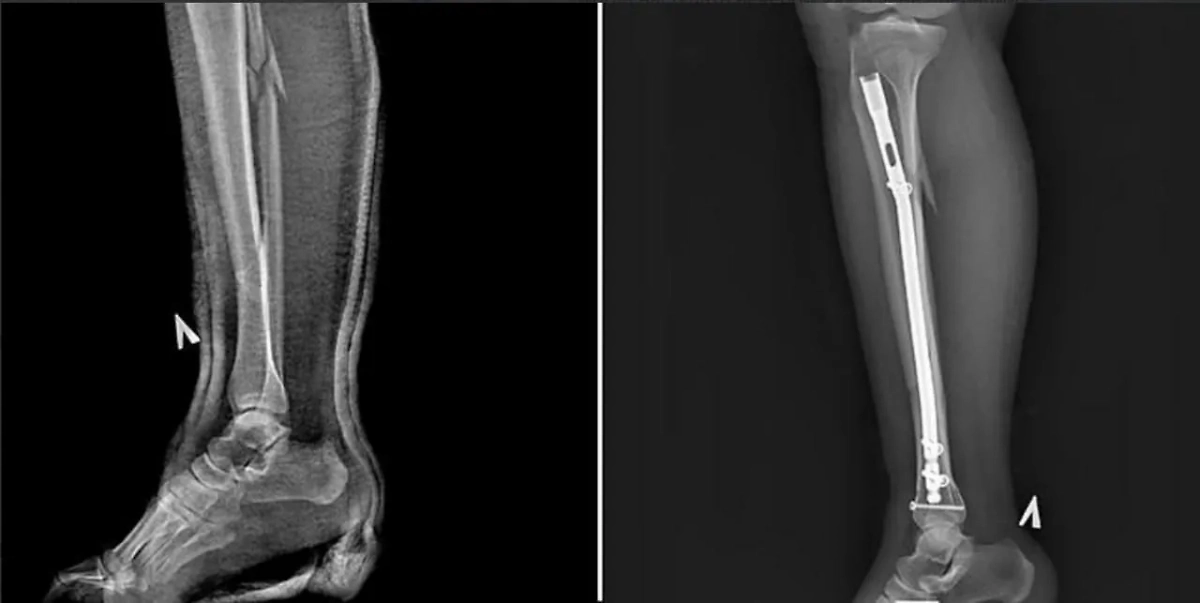

Перелом в трёх местах из-за каблука. Фото предоставлено Life.ru

Врачи подмосковного города Пушкино смогли спасти девушку, которая получила три перелома ноги из-за каблука. 30-летняя дама попала в яму на 12-сантиметровых шпильках и обратилась в отделение травматологии Пушкинской клинической больницы имени профессора В.Н. Розанова. В результате травмы она получила оскольчатый перелом костей голени, большой берцовой и малой берцовой костей.

"Под спинальной анестезией мы провели остеосинтез, то есть сращение обломков костей, чтобы правильно их закрепить, использовали штифты и винты. Остеосинтез позволяет уйти от традиционного и привычного гипса и, соответственно, исключает вероятность вторичного смещения, а также последствий в виде тромбоза, остеопороза, артроза. На повреждённую ногу пациентка смогла наступать вечером уже в день операции", — рассказал травматолог-ортопед Александр Первухин.